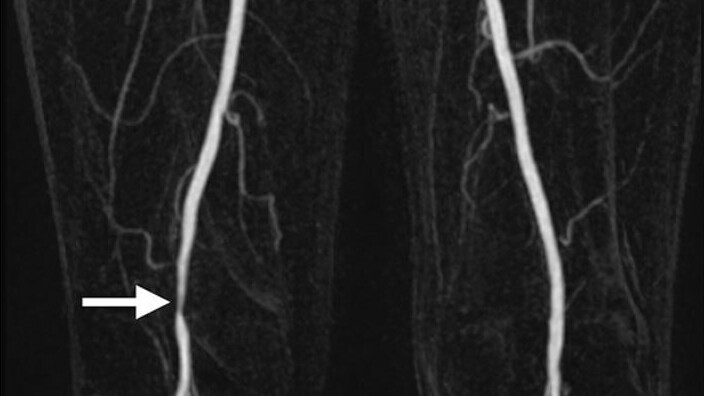

A cramping thigh or calf pain after walking a certain distance also known as claudication could indicate a narrowing in the blood supply to your legs.

A history and examination is undertaken by your vascular surgeon. Assessments available in outpatients include a doppler probe or ultrasound to assess the blood supply to your legs